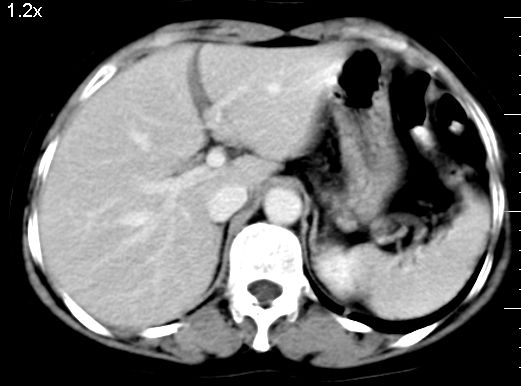

f、52岁,反复上腹部疼痛2年。肺结核病史10多年,胸片双上肺结核纤维化。

ct表现:

肝大小形态未见异常,肝内外胆管无扩张,肝s8段见一动脉期明显血管样强化结节,门脉期呈高密度,延迟期呈等密度,胆囊不大,增强扫描见胆囊及胆囊颈管壁增厚,有强化。

双肾灌注良好,代谢增快,动脉期肾盂见造影剂,左肾下极背侧见一略低密度病灶,延迟期见似不强化囊肿,双侧肾上腺未见异常。

胰腺及脾未见异常。肾门水平腹膜后见小淋巴结。腹腔未见积液征象。

诊断:

1、胆囊炎(轻度)。

2、肝s8段结节,考虑小血管瘤。

3、左肾下极低密度灶,考虑囊肿可能性大,建议随访,除外小肾癌(无强化可以基本除外)。

4、目前ct表现尚不能解释患者上腹部疼痛,建议上消造影检查,除外胃炎等疾患。